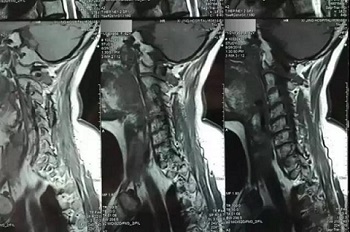

片子反光,背景无透射光

把片子直接贴在窗户玻璃上拍,窗户外面的风景透过片子拍入了照片上,图片的下半部分,可以隐约看到窗户外面的建筑,影响医生阅片,不能获取有价值的磁共振信息。